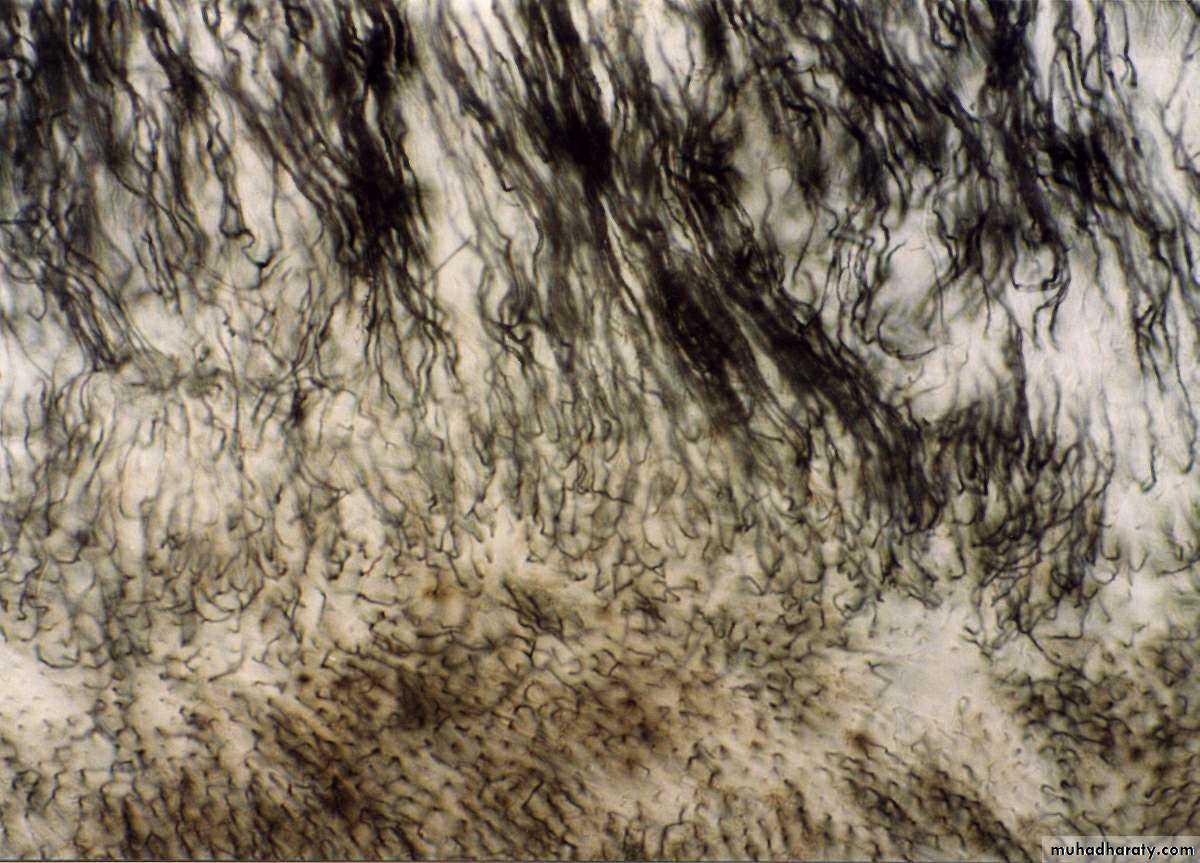

Contour line of OwenInterglobular Dentin

Calcification of dentin in some areas occurs in a form of globular pattern.These globules fuses together to form homogenous substance.

CementumInterglobular dentin

(Size) Large(Cause) Areas of unmineralized or hypomineralized dentin (sometimes present).

(Site) Appear in the crown just below mantle dentin.

(IL) Follow incremental line pattern

In badly formed tooth it appears in the root dentin